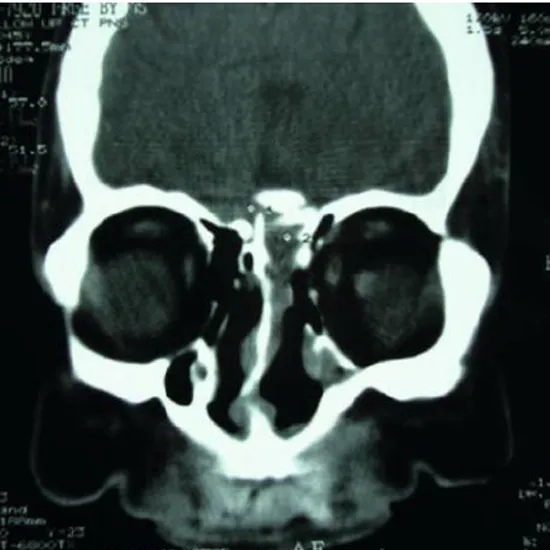

CECT PNS SAGITTAL is a contrast-enhanced computed tomography paranasal sinus sagittal view. This is an imaging scan that is used to detect the tumors, fluid accumulation, inflammation, fracture and injury that affect the nasal cavity. In this scan, contrast media is used to enhance the view and obtain clear images of the sinus cavity, sideways from the sagittal view (the right to the left side).

CECT (Contrast-enhanced Computed Tomography) screening of the PNS Sagitta is a non-invasive radiology test used to evaluate the paranasal sinus and surrounding tissue. CECT PNS Sagittal is done to look for the conditions of the paranasal sinus and the surrounding area.